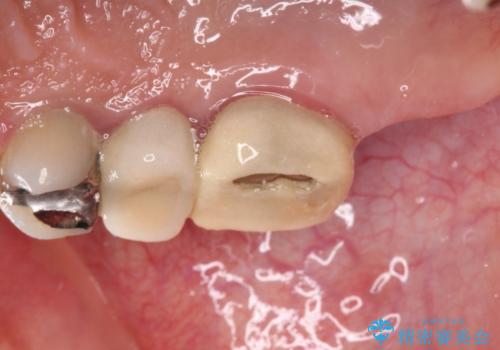

- 奥歯を治療しようと他院で開始したものの、放置してしまったとのことで来院された患者様です。

外れてしまった銀歯や穴の空いた仮歯などあり、適合の悪い被せものと合わせて、セラミッククラウンやセラミックインレーにて治療と行うこととしました。